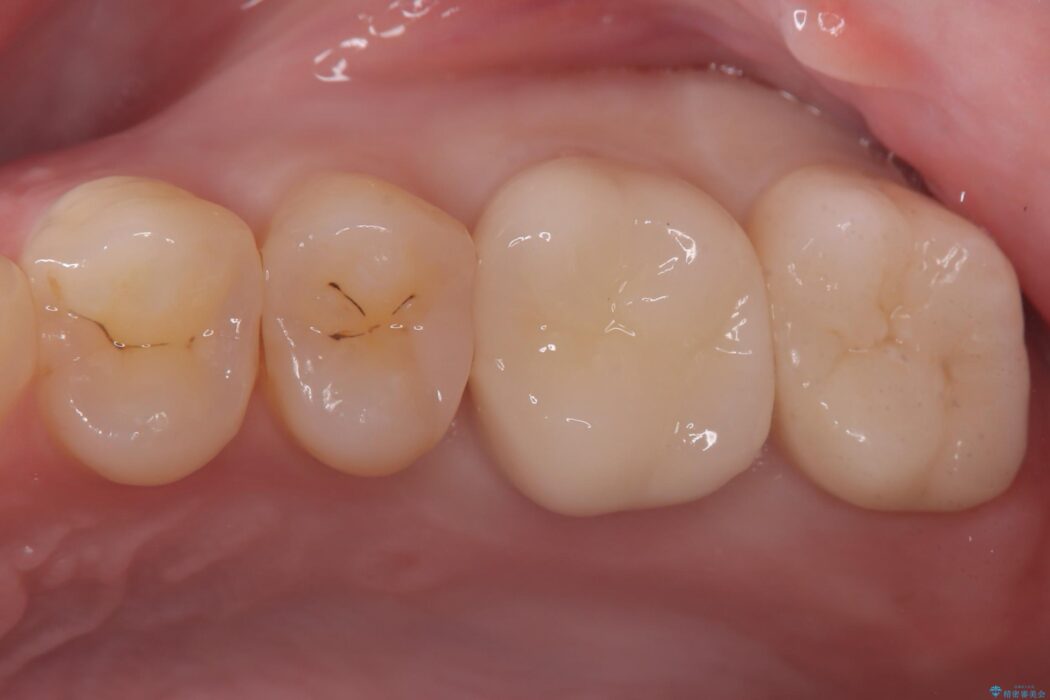

経過観察と土台作り: 一定期間の経過を観察し、痛みや炎症がないことを確認。神経の生存を確認した上で、セラミックを支えるための土台を精密に構築しました。

セラミックによる修復: 最終的な補綴物にはセラミックを使用しました。高い適合性により、二次的な虫歯のリスクを抑えつつ、天然歯のような自然な咬み心地と美しさを再現しました。